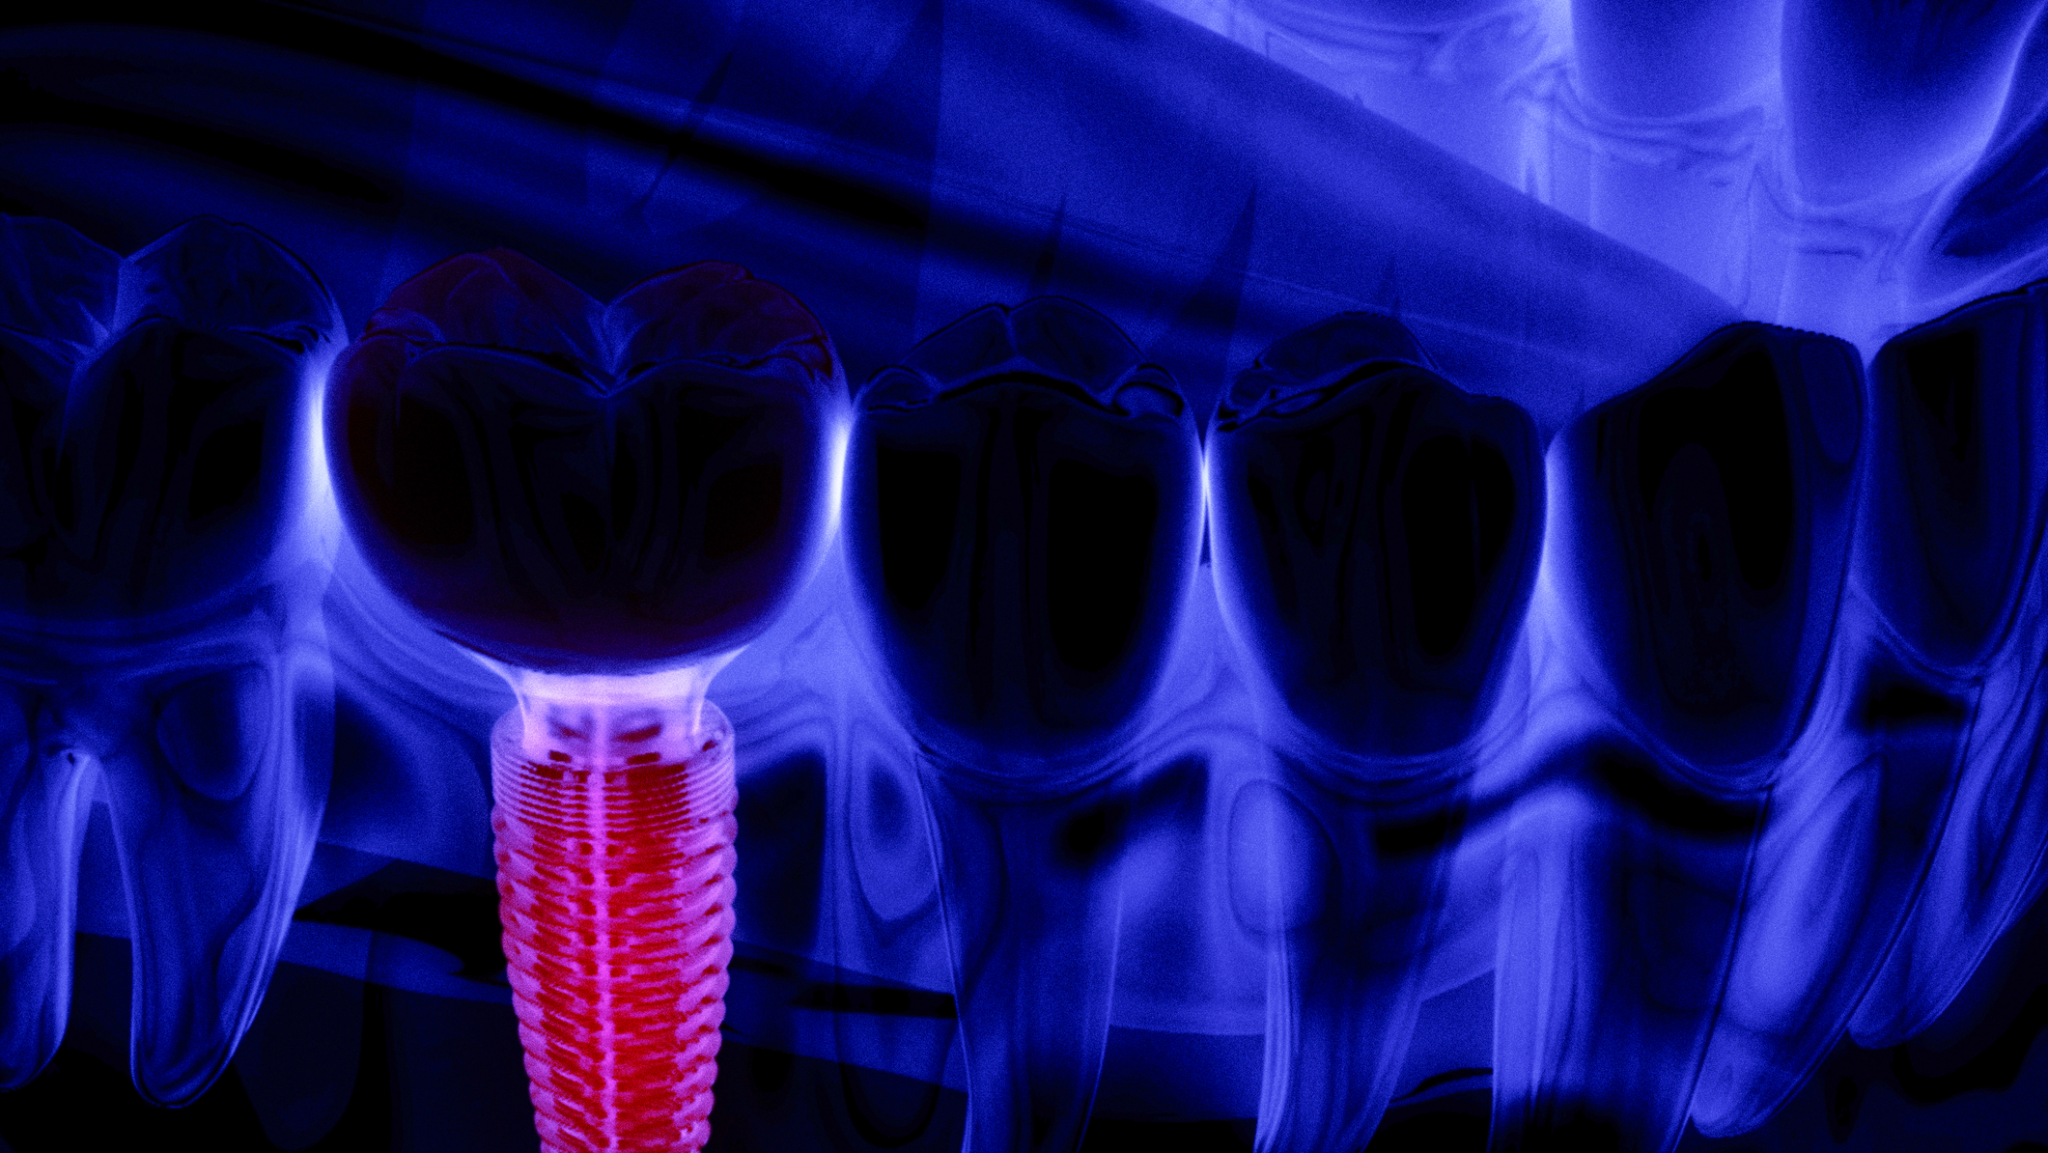

A new U.S. study published Friday in JAMA Health Forum warns that eliminating fluoride from community water systems could lead to increased tooth decay in children and drive up dental costs by an estimated $9.8 billion over five years. “Fluoride replaces weaker ions within tooth enamel, making it stronger and less susceptible to tooth decay … Read more